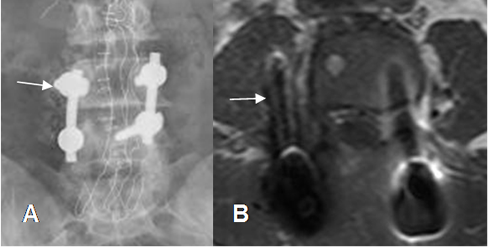

Fig 137. Mal posición de tornillos.

A: Rx AP y B: RM axial en T1. Tornillo superior derecho mal localizado, por fuera del pedículo y en el interior del músculo psoas.